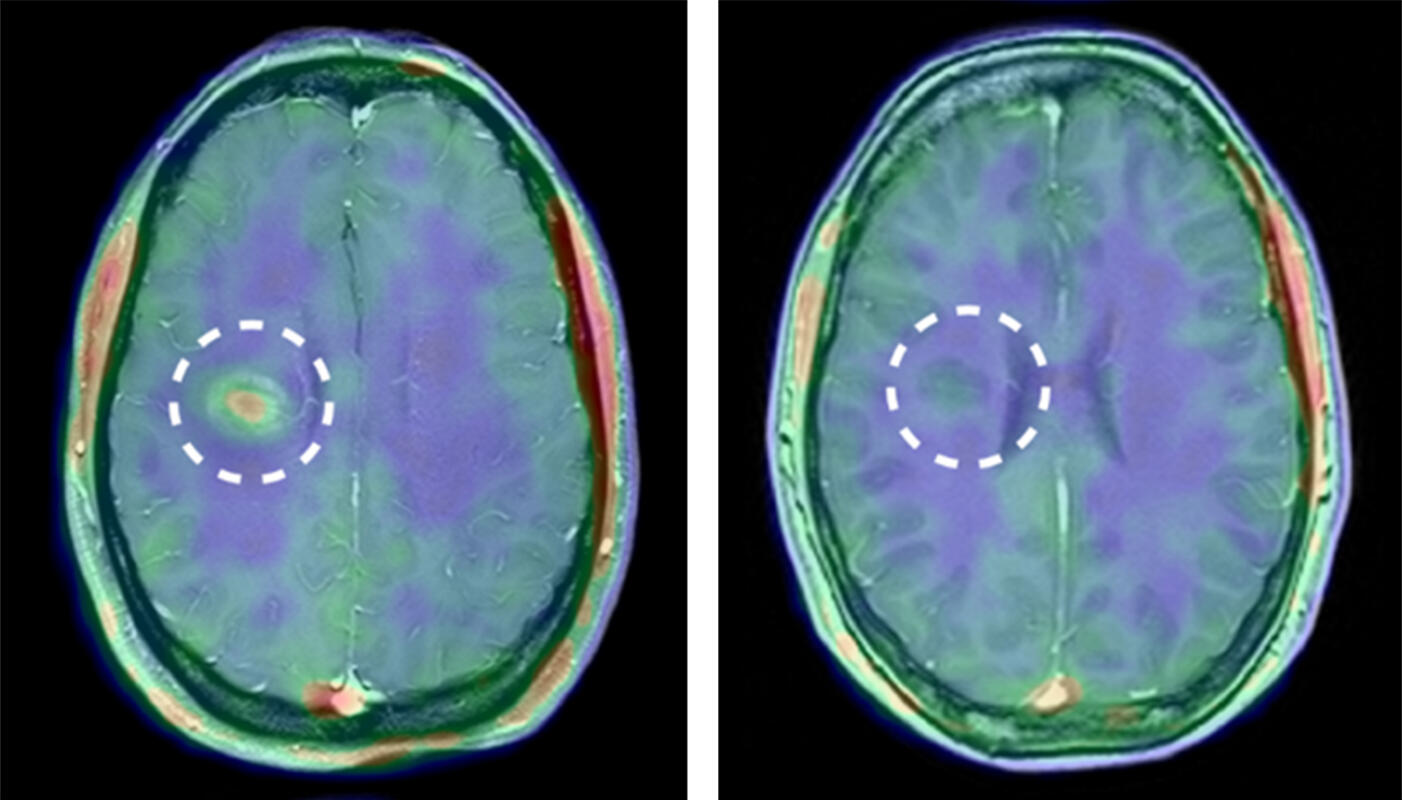

Entzündung im Gehirn eines Menschen vor Therapie (links) und nach Therapie (rechts), dargestellt mit kombinierter Positronen-Emissions-Tomographie und Magnet-Resonanz-Tomographie (PET-MRT).

Die Ergebnisse waren eindrucksvoll: Der MMP-Tracer reicherte sich im menschlichen Gehirn an, und zwar schon bevor mit dem traditionellen Verfahren eine Schädigung der Blut-Hirn-Schranke zu sehen war. Die Forscher konnten belegen, dass auch beim Menschen MMPs aktiv sind, bevor Immunzellen die Blut-Hirn-Schranke durchwandern. „Es war schon etwas Besonderes, dass man bei einem Patienten untermauern konnte, was man zuvor in der tierexperimentellen Grundlagenforschung festgestellt hatte“, sagt Dr. Sven Hermann, Nuklearmediziner und Experte für Kleintierbildgebung. „Das ist doch der Wunsch eines jeden Wissenschaftlers.“ Auch die Erwartung, dass der Tracer sich nach anti-entzündlicher Therapie weniger anreicherte, wurde erfüllt.